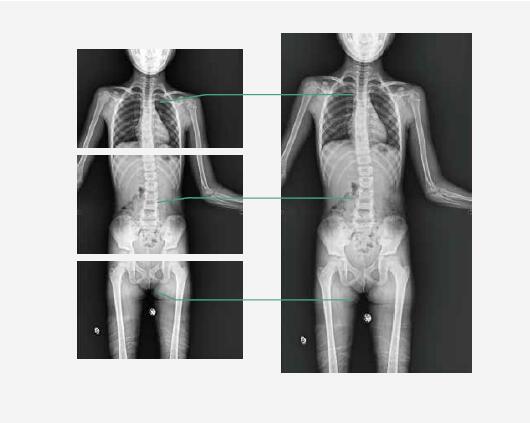

Auto stitching (Option)Captured image can be automatically stitched together by the system, giving a long image that extend across the larger areas of the body.

Captured image can be automatically stitched together by the system, giving a long image that extend across the larger areas of the body.